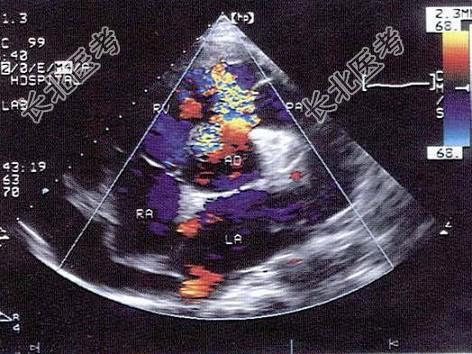

- 单项选择题该病例最可能的诊断为   (   )

A、室间隔缺损

B、主动脉右冠窦瘤破裂

C、右室流出道狭窄

D、主动脉右冠瓣脱垂

E、房间隔膨出瘤